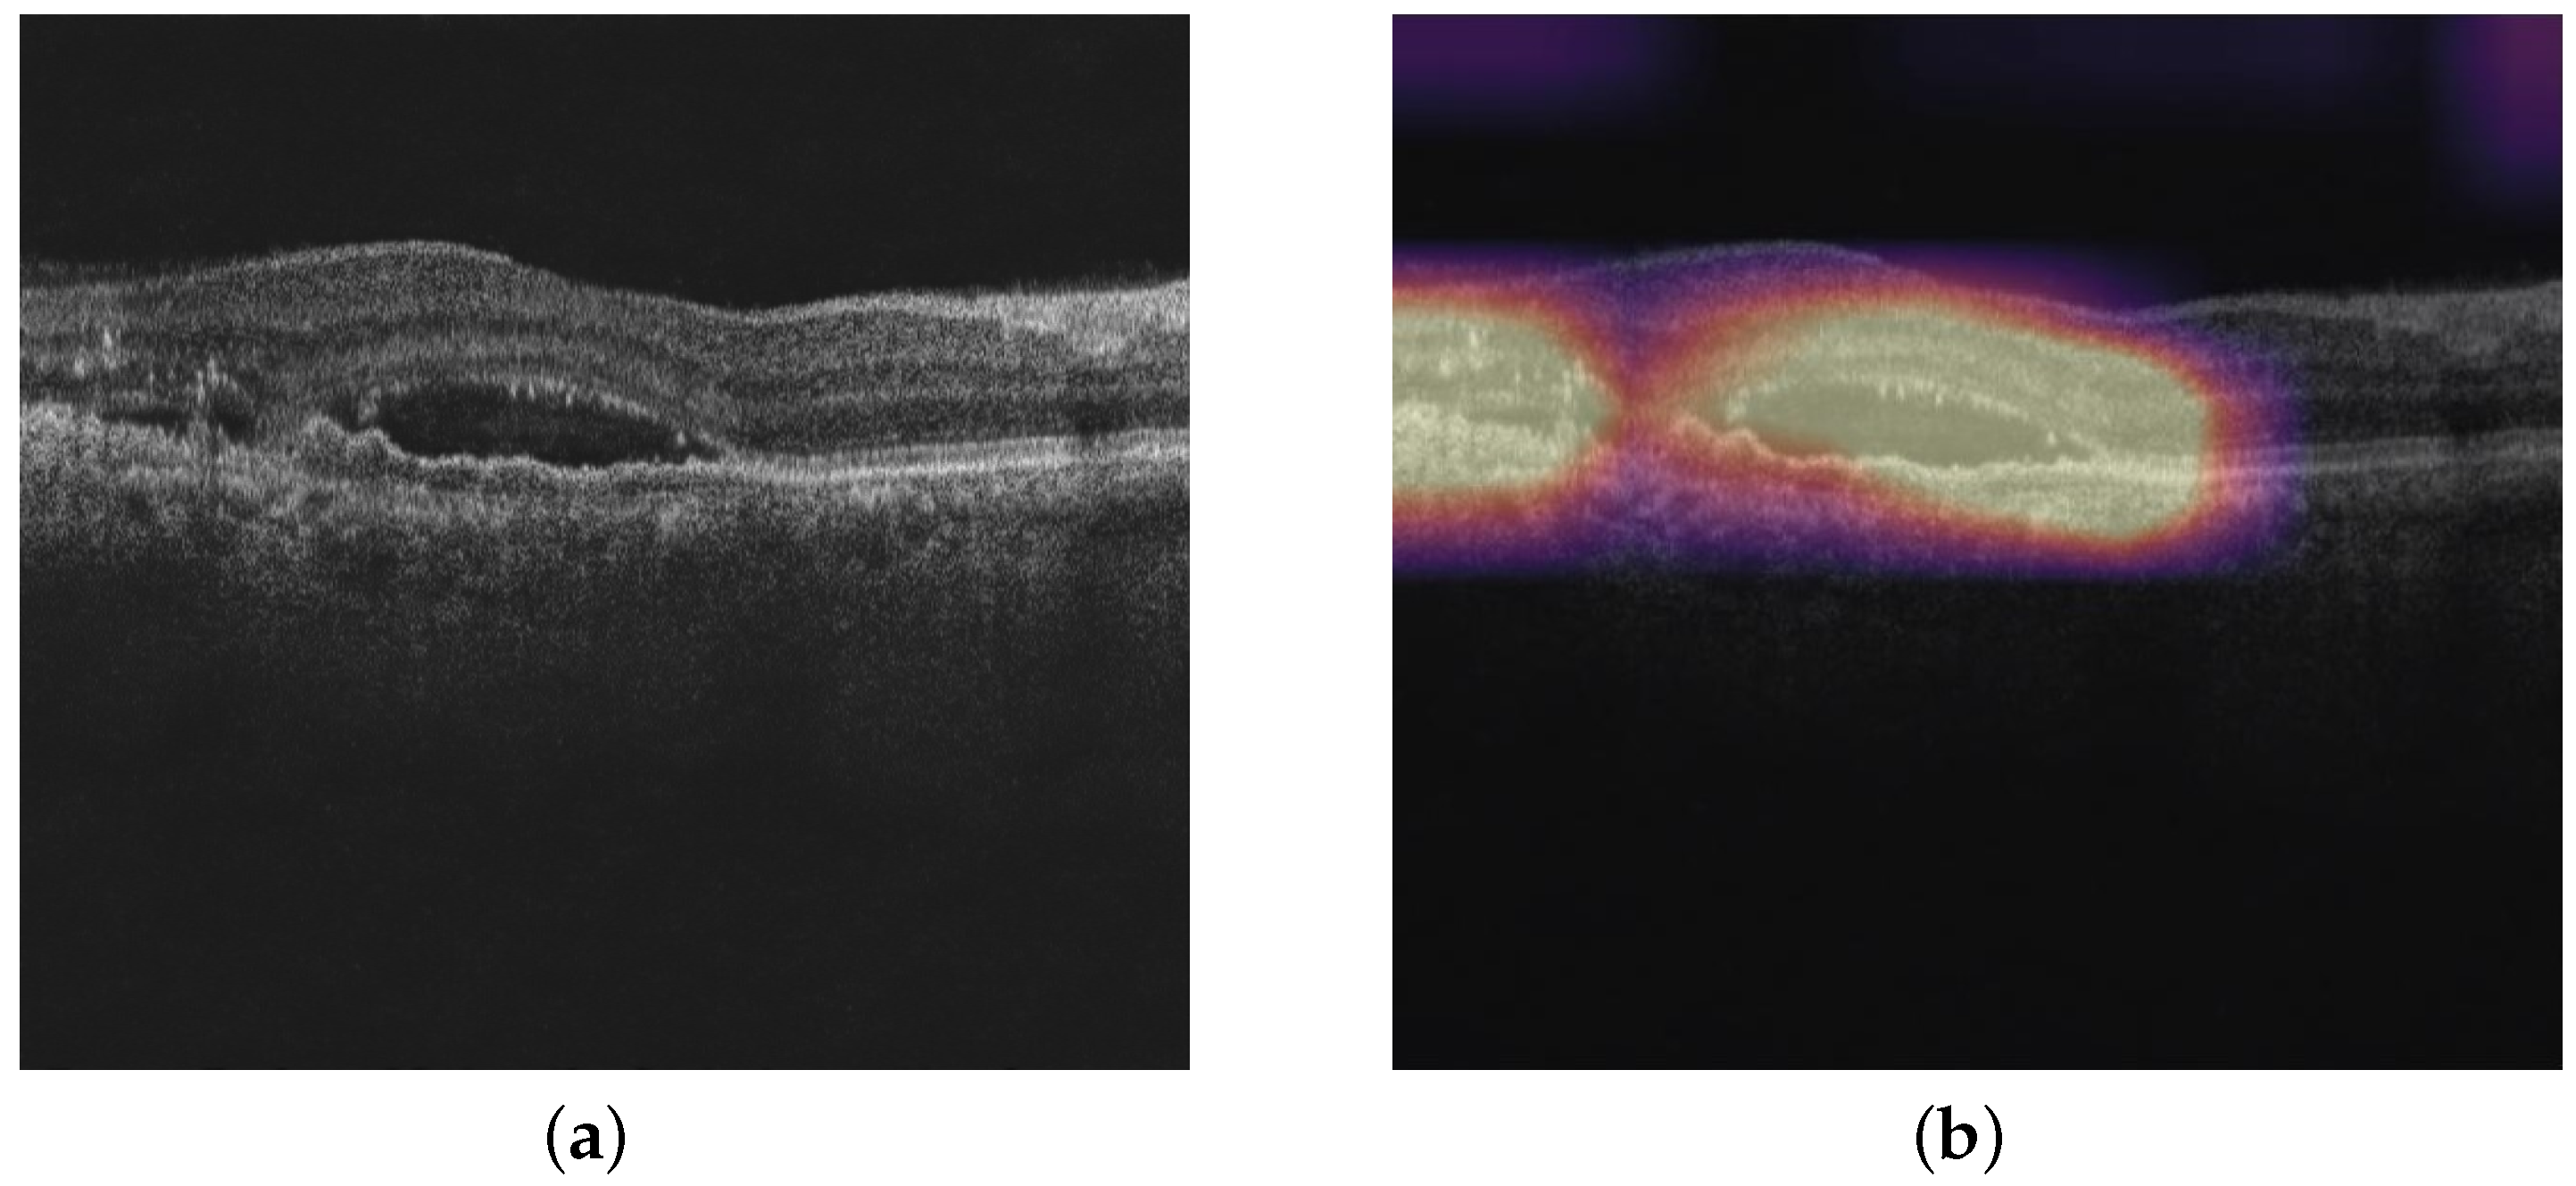

Figure 1 shows an OCT image in which all three pathologies, namely IRF, SRF, and PED, are present.

Due to the black-box nature of the deep-learning-based classification models, there is a need for explainability of the model. We consider standard visualization-based techniques such as GradCAM, GradCAM++, Score-CAM, Ablation-CAM, and Self-Matching-CAM on the binary classification models of IRF, SRF, and PED. These visualization techniques help doctors understand why the model made a certain decision for an image by highlighting relevant parts of the image. Figure 5b shows the Grad-CAM output of the GCDS denoised OCT image shown in Figure 5a. In the heat map, the yellow region indicates the most relevant region, and the relevance decreases as the color changes from yellow to blue.

Figure 1. Various pathologies of interest that are observed in OCT images: IRF: Intraretinal Fluid; SRF: Subretinal Fluid; and PED: Pigmented Epithelial Detachment.

Figure 5. (a) GCDS denoised OCT image and (b) GradCAM output.